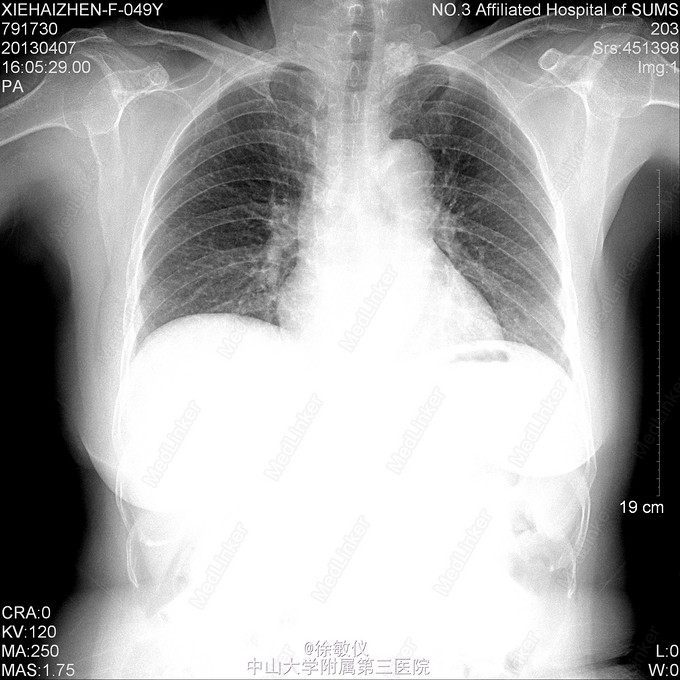

从这张胸片中你看出了什么端倪没?——大家来找茬。。。

大家都会看的胸片

看这张胸片,你的诊断是什么。。。